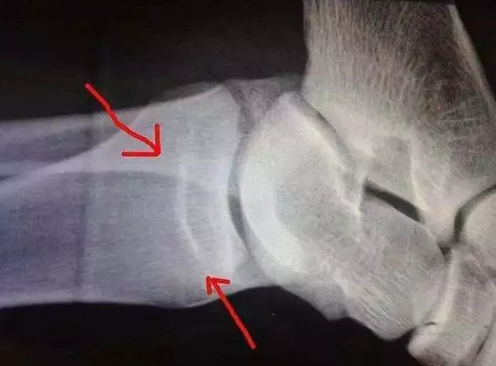

想要寶寶長得高,在骨骺線閉合時間之前,及時的補充營養,多運動鍛煉,才能讓孩子有一個理想的身高,注意骨骺線閉合的時間,那么骨骺線什么時候閉合?怎么預防?下面八寶網小編帶來介紹。

一般情況下,骨骺線閉合后就預示著人們身高基本停止增長,但是也不一定沒有增高的可能,只要通過科學方法就仍然有長高機會。